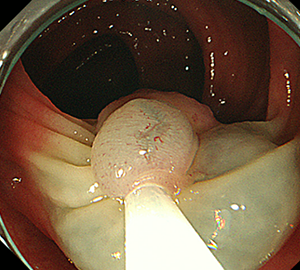

内視鏡的粘膜切除術(EMR)

外来にて切除することの出来ない、比較的大きめの大腸ポリープや平坦な病変などの切除の際に行います。

| 1:ポリープを見つけ、NBI併用拡大観察をした後、 | 2:ポリープ直下の粘膜下層に局注液を注入し盛り上げます。 | |

| 3:ポリープをスネアに通し、周囲の正常粘膜を入れて病変を絞扼 | 4:電気を流してして切除します。 | |

| 5:切除面をクリップで縫合閉鎖し、回収した検体の病理検査に提出します |